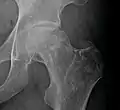

Radiography of avascular necrosis of left femoral head. Man of 45 years with AIDS.